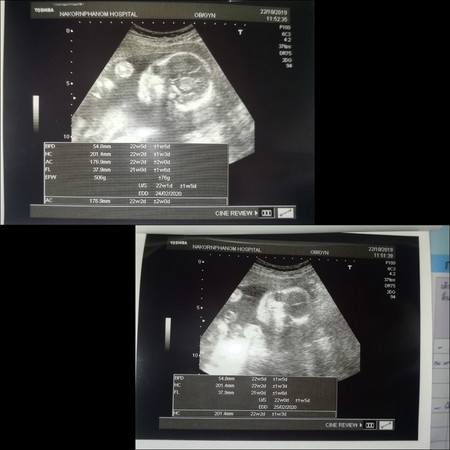

อัลตร้าซาวด์ ครั้งแรกเมื่อวาน 5เดือนกว่าๆ คุณหมอบอก60%เป็นผู้หญิง แต่ยังไม่ชัวร์จ้า